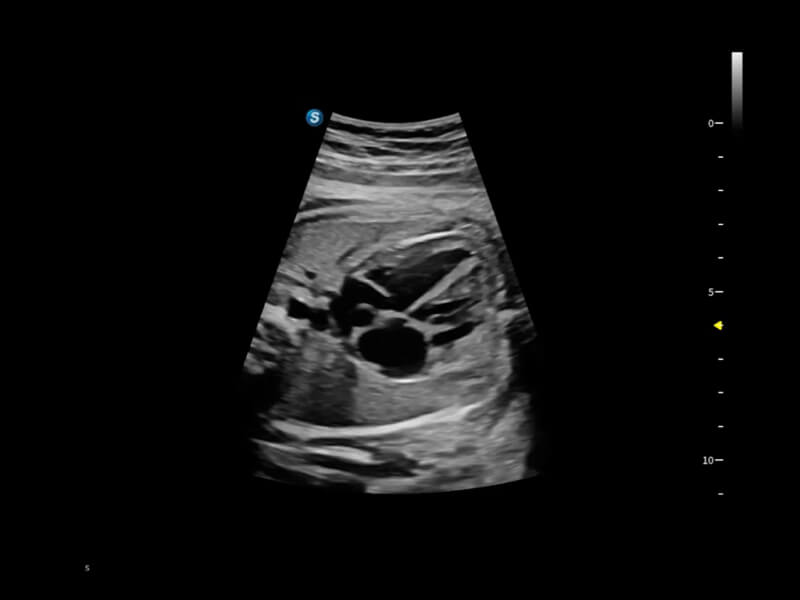

豐富的血流動(dòng)力學(xué)檢測(cè)技術(shù),可在不同醫(yī)療場(chǎng)景中高效捕捉血流信號(hào),助力臨床診療。

在傳統(tǒng)血流的基礎(chǔ)上優(yōu)化掃查和算法策略,能夠更好的抑制組織信息,提煉紅細(xì)胞運(yùn)動(dòng)信息,得到更高幀頻,高靈敏度和分辨率的血流信號(hào),還原更真實(shí)的血流動(dòng)力學(xué)。

通過光照模型,使二維血流顯示出立體的效果,增加血流的敏感性、成束性,減少外溢??梢院推渌煌难骷夹g(shù)聯(lián)合使用,融合不同技術(shù)的優(yōu)勢(shì)。輕松應(yīng)對(duì)微小血管,增強(qiáng)血流的立體效果,提升視覺敏感性。

通過創(chuàng)新的Matrix E自適應(yīng)濾波算法,能有效濾除軟組織和噪聲信號(hào),最大限度保留超低速微細(xì)血流的信號(hào);結(jié)合超長時(shí)間域算法,極大提升細(xì)微血流的敏感性和空間分辨率,更真實(shí)的反應(yīng)組織、包塊的血流灌注情況。